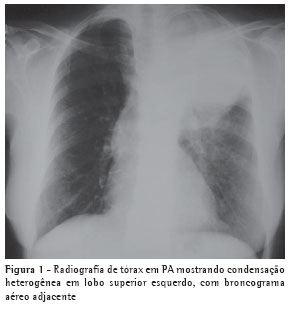

O radiograma torácico apresentava imagem densa, tipo massa, em lobo superior esquerdo (Figura 1). A tomografia computadorizada de tórax (Figura 2) confirmou a presença de massa heterogênea em lobo superior esquerdo, com broncograma aéreo adjacente à mesma, sugerindo lesão expansiva neoplásica. A paciente não conseguiu realizar coleta de escarro para exame devido à pequena quantidade de secreção.

Não há padrão radiológico característico, embora nódulos únicos ou múltiplos, bem definidos e não calcificados, sejam os mais comuns, podendo simular radiologicamente neoplasia.(5,9) Foram descritas alterações radiológicas tais como infiltrado (62%), nódulos (38%), massa (19%), lesão cavitada (14%) e derrame pleural (3%), sem um padrão de distribuição anatômica e sem adenomegalia hilar ou mediastinal associados. Há relatos na literatura de empiema, pneumotórax e envolvimento pleural sugerindo tumor de Pancoast(13) e massa pulmonar invadindo parede torácica.(14) A tomografia computadorizada de tórax corrobora os achados radiológicos, fornecendo maiores detalhes para o diagnóstico diferencial(11) e, quando necessário, auxilia na programação da propedêutica diagnóstica invasiva. A paciente descrita apresentava massa pulmonar simulando neoplasia.